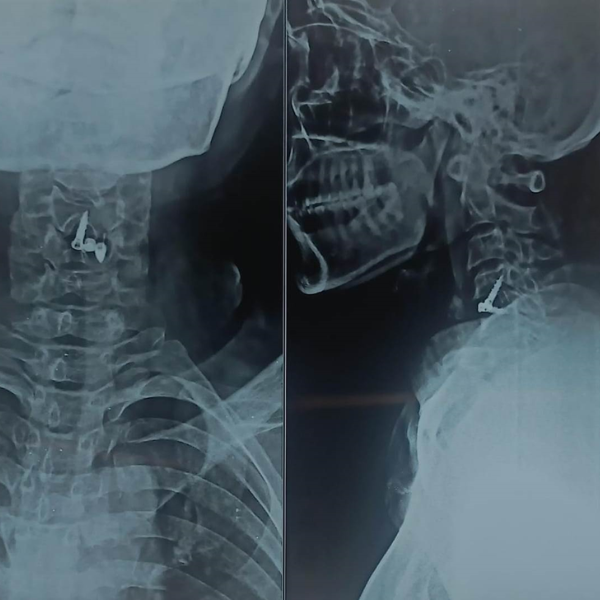

Cervical Disc Prolapse Treatment

Cervical Disc Prolapse Advanced Cervical Spine Care by Dr. Nitish Agrawal – Best Spine Surgeon in Pune Cervical Disc Prolapse, commonly known as slip disc in the neck, occurs when a disc in the cervical spine bulges or herniates and compresses nearby nerve roots or the spinal cord. This condition…